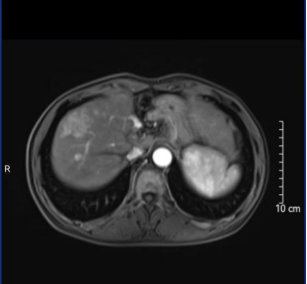

面对一位病情极为复杂的患者——肿瘤多发子灶盘踞右肝,剩余左半肝体积微小,健康肝脏储备严重不足,传统观念中视为“不可切除”的禁区。肝肿瘤切除联合消融面临快速复发风险,介入联合靶向、免疫治疗转化过程中左肝转移风险高企。

在此生死攸关之际,依托“广龙合作”搭建的快速响应与深度协作平台,龙岩市第二医院肝胆外科团队迅速与陈亚进教授团队远程联动,展开多轮线上多学科会诊。双方专家智慧碰撞,达成共识:积极保护健康左肝,同时实施系统抗肿瘤治疗,静待左肝增生、肿瘤活性控制,即实施双转化治疗。被誉为肝胆外科手术“皇冠明珠”的ALPPS技术,成为照亮患者生命之路的“希望之光”。